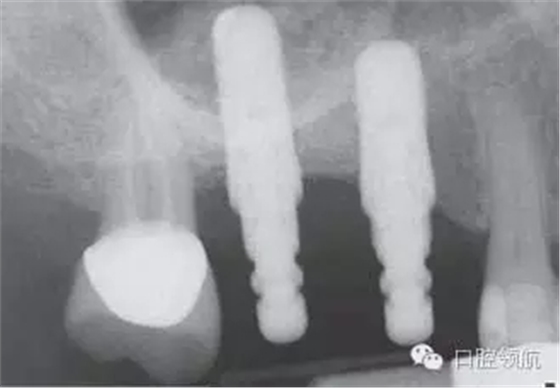

8個(gè)月后,植入2顆種植體,并獲得了良好的初期穩(wěn)定性(圖10)。雖然計(jì)劃上頜竇底提升同期植入種植體,但如果出現(xiàn)上頜竇黏膜穿孔時(shí),不建議同期植入種植體。

圖10 術(shù)后8個(gè)月植入種植體時(shí)的X線片。